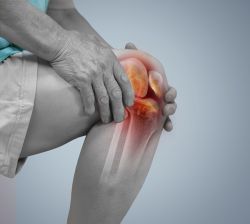

Viêm khớp là tình trạng viêm xảy ra ở một hoặc nhiều khớp trong cơ thể. Các triệu chứng chính của bệnh viêm khớp là sưng đau và cứng khớp, thường nặng dần theo thời gian. Hai loại viêm khớp phổ biến nhất là thoái hóa khớp và viêm khớp dạng thấp.